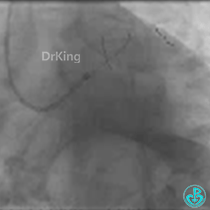

为什么要用到微导管KDLC双腔微导管在反转导丝中的应用_https://www.jmylbn.com_新闻资讯_第3张

正如预测的一样,分支导丝始终无法通过分支开口,采用双腔微导管辅助翻转导丝技术顺利进入。

从球囊扩张不充分可以看出病变重,病变较硬且成角严重,计划使用切割球囊处理。

用2.5×10mm球囊以10atm×10s扩张。